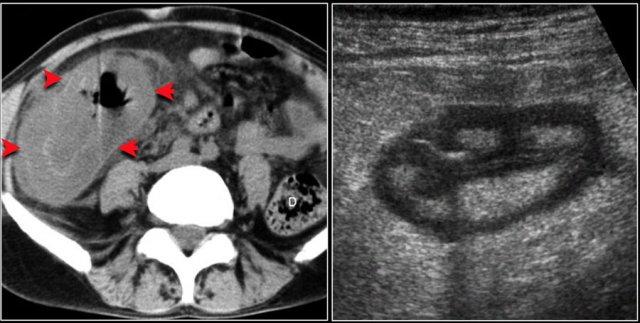

Đôi khi, tái tạo ảnh mặt phẳng coronal dạng lát cắt dày (thick slab coronal reconstructions) có thể hữu ích trong việc đánh giá mức độ ngấm thuốc.

Điều này được minh họa rõ ràng ở bệnh nhân này, trong đó hỗng tràng ngấm thuốc tốt (vùng xanh lá), trong khi hồi tràng giảm ngấm thuốc (vùng đỏ) do thiếu máu cục bộ.

Đây là một trường hợp tắc ruột quai kín khác.

Lưu ý sự khác biệt về mức độ ngấm thuốc giữa các quai ruột bình thường không giãn (mũi tên xanh lá) và các quai ruột giãn bị thắt nghẹt (mũi tên đỏ).

Ở trung tâm là các mạch máu mạc treo bị xoắn vặn (mũi tên vàng).